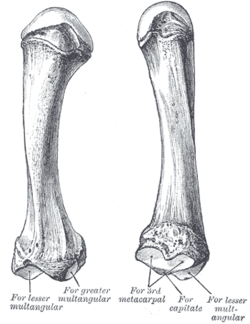

Carpometacarpal bossing (or metacarpal/carpal bossing is a small, immovable mass of bone on the back of the wrist. The mass occurs in one of the joints between the carpus and metacarpus of the hand, called the carpometacarpal joints, where a small immovable protuberance[1] occurs when this joint becomes swollen or bossed.

The joint between the index metacarpal and the capitate is a fibrous non-mobile joint. Some people have a gene that leads to this growth. It looks like arthritis (bone spurs on each side of the joint) on X-ray. It looks like a ganglion on the hand, but more towards the fingertips.

The carpometacarpal joint is usually found at the base of the second and third metacarpal bones at the point where they meet the small bones of the wrist.[2]